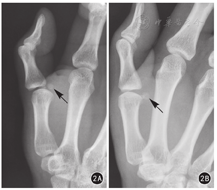

所有患者常规拍摄拇指正、侧位X线片。侧位X线片可见拇指掌指关节过伸,桡、尺侧籽骨均向远端移位,但桡侧移位程度更大,且桡侧籽骨与掌骨头关节面出现不匹配(图2)。术前均行CT检查。CT三维重建显示尺侧籽骨和掌骨头之间有正常的关节间隙,而桡侧籽骨骑坐于掌骨头上,二者之间的关节间隙消失;CT矢状位重建显示桡侧籽骨掌骨关节间隙消失,并可见桡侧籽骨除近侧缘外均由软组织包绕(图3)。